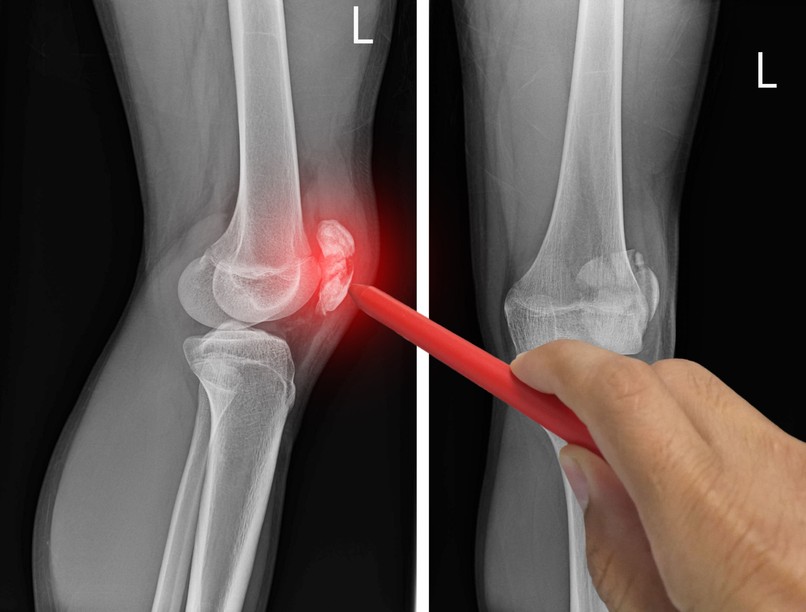

Egy 40 éves kor felett egyre többen találkoznak a fájós térd problémájával, ami az évek alatt kialakuló porckopásnak köszönhető. Az osteoathritis kockázatát csökkenthetjük rendszeres sporttal. Dr. Páll Zoltán, a Budai Fájdalomközpont sebésze, traumatológus, sportorvos arról beszélt, hogy nem mindegy, milyen jellegű mozgást végzünk.

Porckopás miatt fáj

Míg a fiataloknál leginkább a sportolás közben szerzett sérülés vagy a nyálkatömlő gyulladása eredményezi a térdfájdalmat, addig az idősebbeknél a leggyakoribb ok az ízületek kopása, elhasználódása, azaz a korai osteoarthritis. Az osteoarthritis az ízületi porcok állapotromlásának végső és fájdalmas eredménye.

A porc ugyanis "kipárnázza" a csontok közti területet, vagyis ha elvékonyodik, a csontok dörzsölik az ízületek szélét, amely ráadásul igen gazdag idegvégződésekben, tehát fogékonyabb a fájdalomra is. Bár mindenki szembesülhet a porckopással, mégis azoknál alakul ki korábban, akik régebben atletizáltak, vagy fiatalabb korukban térdsérülést szenvedtek. Amennyiben fájdalmat és merevséget tapasztalunk reggel vagy fizikai megterhelést követően, gyanakodhatunk erre a problémára.